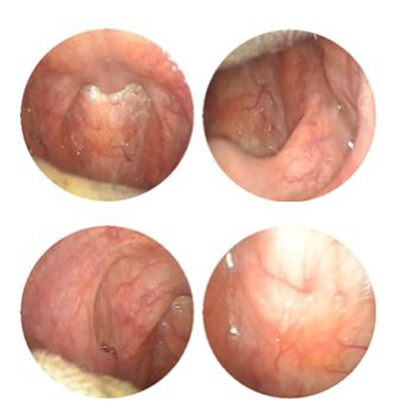

喉部淋巴濾泡增生 (44)

喉部淋巴濾泡增生 (45)

喉部淋巴濾泡增生 (46)

喉部淋巴濾泡增生 (47)

喉部淋巴濾泡增生 (48)

喉部淋巴濾泡增生 (49)

喉部淋巴濾泡增生 (5)

喉部淋巴濾泡增生 (50)

喉部淋巴濾泡增生 (6)

喉部淋巴濾泡增生 (7)

喉部淋巴濾泡增生 (8)

喉部淋巴濾泡增生 (9)

喉部淋巴濾泡增生 (36)

喉部淋巴濾泡增生 (37)

喉部淋巴濾泡增生 (38)

喉部淋巴濾泡增生 (39)

喉部淋巴濾泡增生 (4)

喉部淋巴濾泡增生 (40)

喉部淋巴濾泡增生 (41)

喉部淋巴濾泡增生 (42)